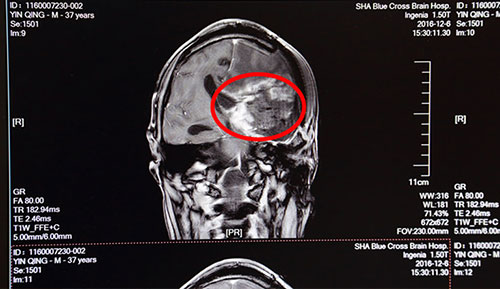

术前影像资料:红圈内为肿瘤物

患者殷某,男,37岁,于2016年04月因胶质瘤复发,行粒子置入术,后出现神志不清伴右侧肢体障碍。在这之前,患者已做过几次肿瘤切除手术及放射性治疗,2011年7月28日在上海某医院第一次行胶质瘤切除术,2015年6月胶质瘤复发第二次行手术切除,期间有过两次化疗,6月复查头颅CT示:胶质瘤较前增大。为进一步治疗,2016年12月6日来到蓝十字脑科医院,门诊以“胶质瘤术后复发”收入神经外科,主诉神志不清伴右侧肢体活动障碍8月余。